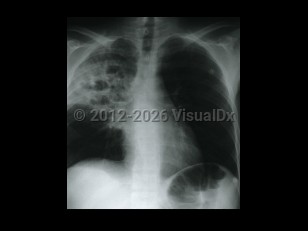

Typically, patients present with pulmonary disease with a subacute course. Main complaints include cough (productive or non-productive), fatigue, fever, and sometimes pleuritic chest pain. Hemoptysis has been reported in 15% of cases. Rhodococcus equi bacteremia frequently complicates pneumonia. Other complications may occur: lung abscess, endobronchial lesions, pleural effusion, empyema, pericarditis, cardiac tamponade, and mediastinitis. Upper lobe cavitary and/or nodular disease is found on radiography, leading to frequent misdiagnosis of tuberculosis. This misdiagnosis can be further compounded by the occasional acid-fast positive stain of the organism. Infection in other locations is usually a late manifestation of pulmonary infection.